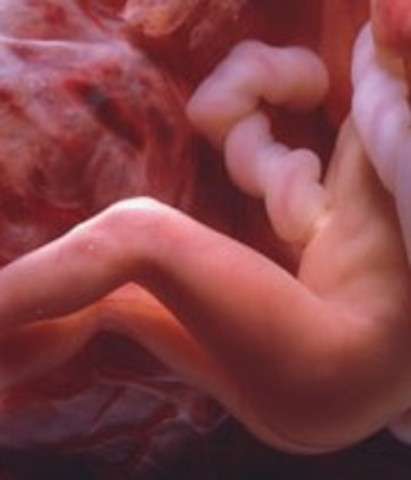

• Week 15 of the Second Trimester

Week 15 of the Second Trimester

The Fetus begins to grow bones and structure comes to the baby's body. Women may start to feel movement.

Facts:

1)Baby is now over 4 inches (10cm) long

and weighs about 2.5 ounces (75 grams).

2)The fetus has an adult's taste buds and may be able to savor the mother's meals.